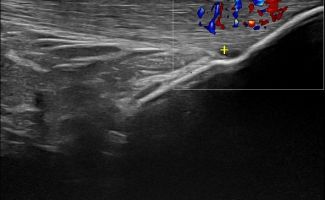

Το Υπερηχογράφημα Γόνατος προσφέρει τη δυνατότητα απεικόνισης παθολογιών στην άρθρωση, τους θυλάκους, τους τένοντες, τους συνδέσμους, τα νεύρα, τα αγγεία και τα μαλακά μόρια της περιοχής του γόνατος.

Η παρουσία συλλογής υγρού, θυλακίτιδας ή υμενίτιδας που ανιχνεύεται με το Υπερηχογράφημα Γόνατος μπορεί να σχετίζεται με ρευματολογική νόσο, όπως:

Αγγεία και Νεύρα Γόνατος

- Θρόμβωση στην Ιγνυακή Φλέβα

- Ανεύρυσμα στην Ιγνυακή Αρτηρία